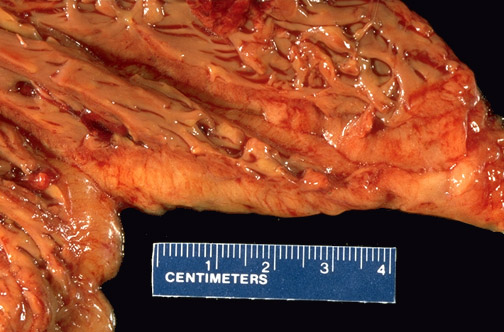

This is right ventricular dysplasia. There is extensive fatty replacement of the right ventricular myocardium (and sometimes the left as well) so that grossly the ventricular wall of the dilated heart is yellowish, as seen here.